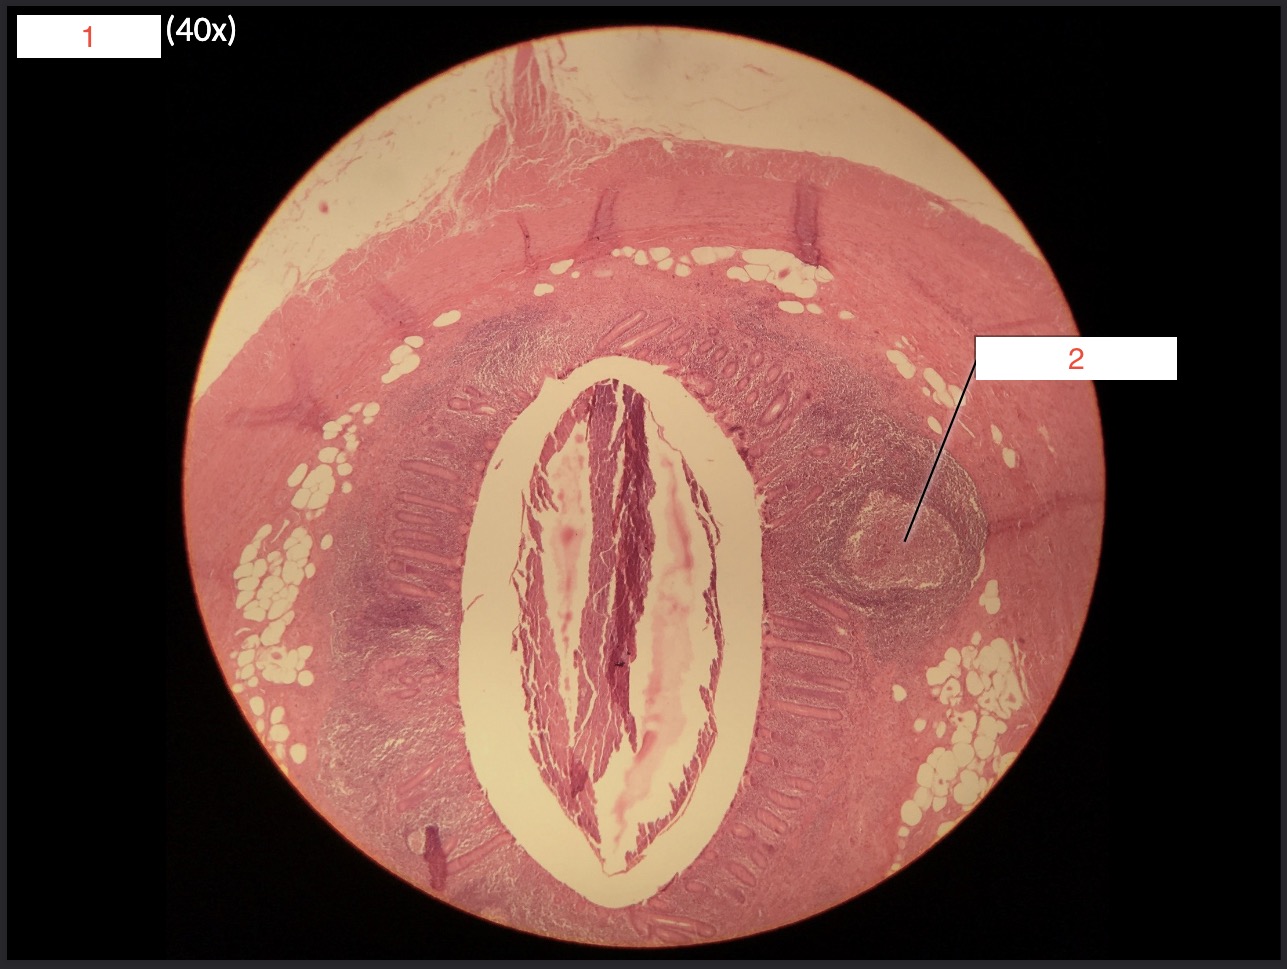

1- What is this slide?

Appendix

2

Peyers patch